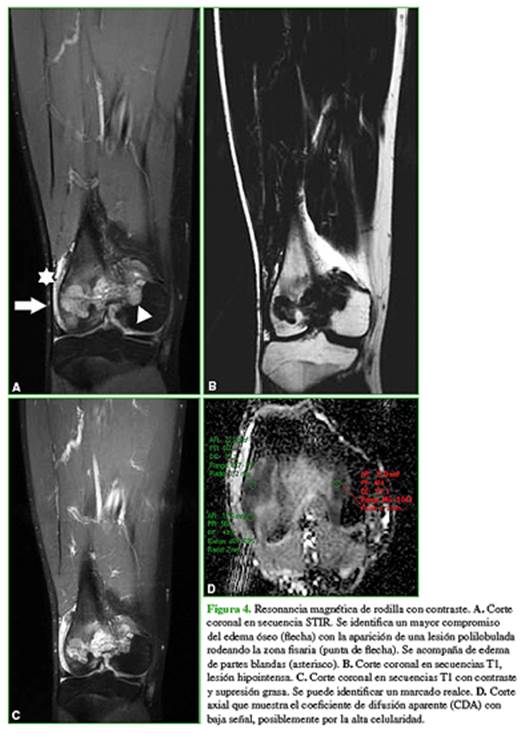

En la resonancia magnética, se observa un mayor edema óseo acompañado de una tumoración que envuelve el cartílago de crecimiento, polilobulada, que adelgaza la cortical posterior, sin romperla (Figura 4A). Persiste la hipointensidad en las secuencias T1 (Figura 4B) y hay un marcado realce tras la inyección del medio de contraste (Figura 4C). En las secuencias de difusión, se comporta hiperintensa, con baja señal en el coeficiente de difusión aparente (valor promedio 0,6 x10-3 mm2/s), lo que plantea la posibilidad de una lesión con alta celularidad (Figura 4D).